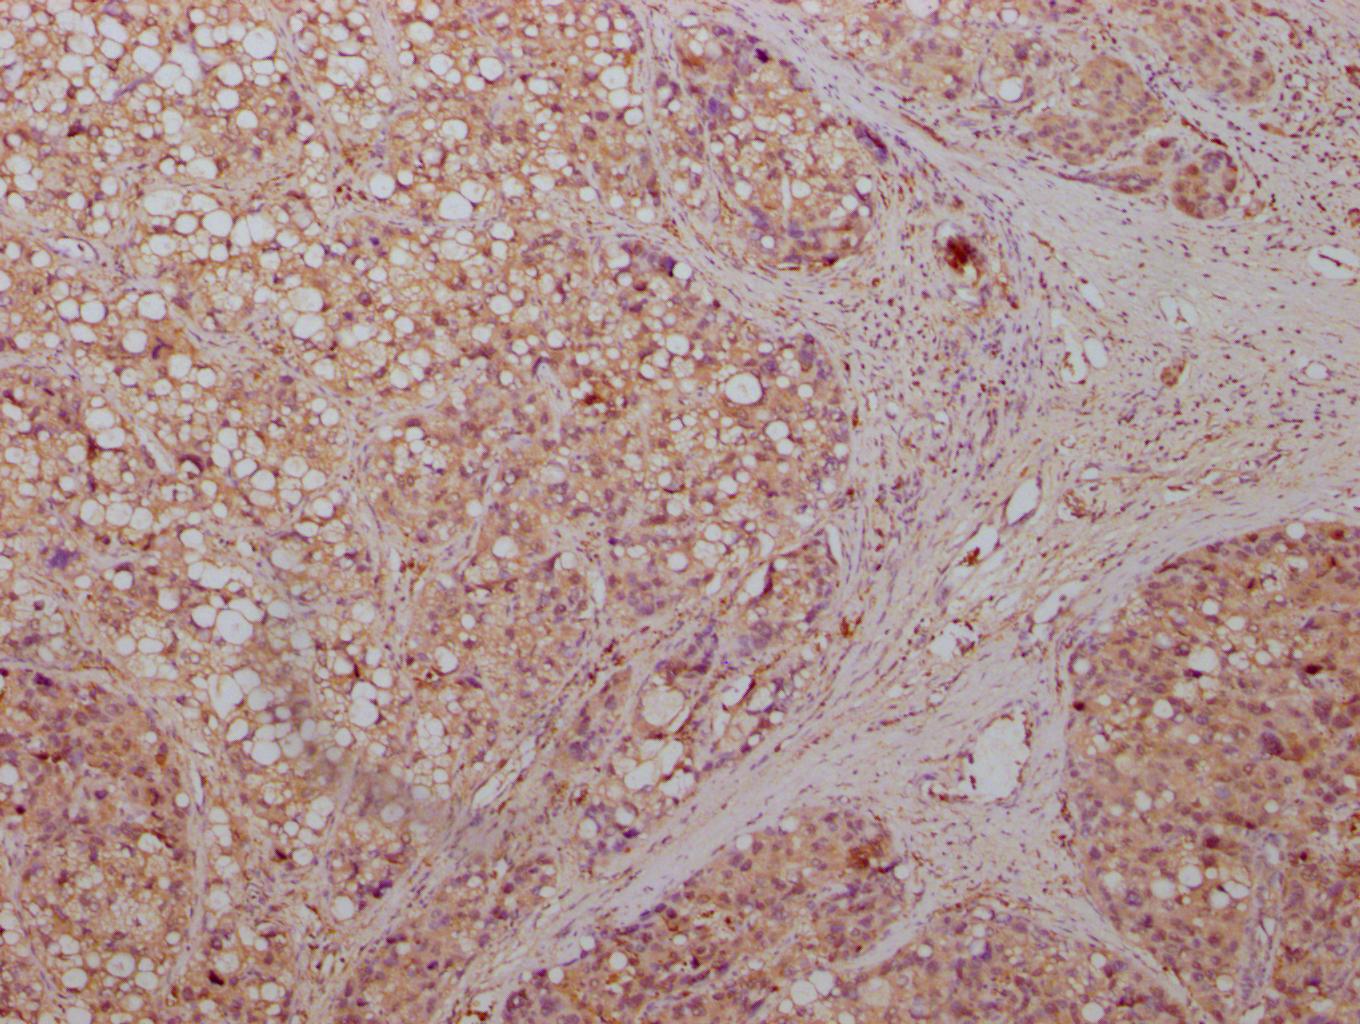

IHC image of CSB-MA007670A0m diluted at 1:500 and staining in paraffin-embedded human pancreas tissue performed on a Leica BondTM system. After dewaxing and hydration, antigen retrieval was mediated by high pressure in a citrate buffer (pH 6.0). Section was blocked with 10% normal goat serum 30min at RT. Then primary antibody (1% BSA) was incubated at 4°C overnight. The primary is detected by a biotinylated secondary antibody and visualized using an HRP conjugated SP system.

-